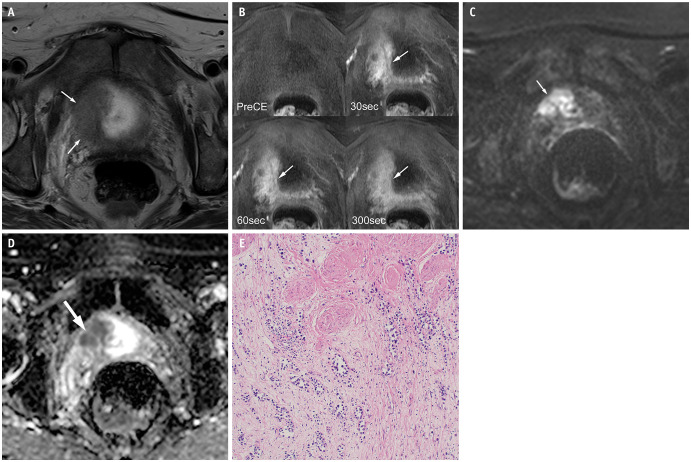

Results: PUC predominantly exhibited diffuse (6/13, 46.2%) or localized (5/13, 38.5%) bladder wall thickening. Diffuse thickening was often associated with a linitis plastica-like appearance. On high b-value diffusion-weighted imaging (DWI), eight and seven cases depending on readers (61.5% and 53.8%, respectively) showed mild hyperintensity or isointensity, with a mean ADC value of 1.1 × 10⁻³ mm²/s. Dynamic contrast-enhanced MRI revealed progressive and prolonged enhancement in 10 cases (76.9%). VI-RADS scores ≥ 4 were observed in 11 cases (84.6%). Histopathological analysis showed that tumors with progressive and prolonged enhancement contained myxoid stroma and some fibrous tissue. Interobserver agreement was excellent for most imaging features, except for good agreement on DWI signal intensity.

Conclusion: PUC demonstrates notable mpMRI features, including localized or diffuse wall thickening (often with a linitis plastica-like appearance), muscle-invasive and advanced disease, progressive and prolonged enhancement patterns, and mild hyperintensity or isointensity on high b-value DWI. These features, which are potentially linked to the myxoid stromal composition of the tumor, suggest that mpMRI may serve as a noninvasive diagnostic tool for this aggressive malignancy. However, further studies with larger cohorts are required to confirm these findings.